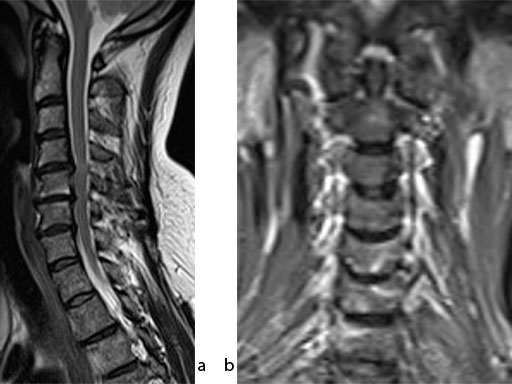

A 51-year-old woman was affected by cervical radiculo-myelopathy due to spinal and neuroforaminal stenosis. The preoperative CT scans are shown at Fig 4 and MRI at Fig 5.

The patient was treated by anterior cervical decompression and fusion (ACDF) with ZERO-P filled with ChronOS. No autologous bone graft was used. Postoperative images are shown (Fig 69).